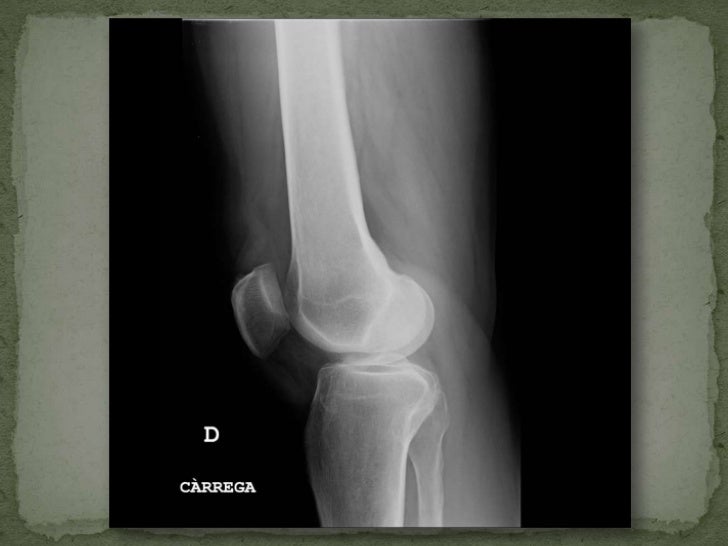

Radiografía tangencial de rodilla 30 60 90 grados (para valorar la rótula)

WebRadiografía axial de rodilla (de 30-60-90 cm) tres proyecciones. La radiografía de rodilla axial muestra el tamaño y la forma de la rodilla. Se realiza para detectar fracturas,. WebUna de las formas más prácticas y rápidas de que los especialistas evalúen esta compleja estructura es mediante una radiografía rodilla, un estudio que permite. WebLa evaluación inicial de la patología de rodilla siempre debe comenzar con la radiología simple. Las radiografías proporcionan información útil, es una prueba de fácil acceso, y. WebRadiografía Axial de Rótula (Variante I) Posición: Paciente de pie frente a la mesa de rayos X. Debe flexionar la rodilla y apoyarla en el borde de la mesa. Chasis (película): El. WebEs un estudio seguro e indoloro en el que se utiliza una pequeña cantidad de radiación para obtener imágenes de los huesos de la rodilla con proyecciones de 30°, 60° y 90°.*. WebLa radiografía de rodilla axial muestra el tamaño y la forma de la rodilla. Se realiza para detectar fracturas, tumores o enfermedades degenerativas de la articulación. Con esta. WebRODILLA AXIAL 30 60 90 GRADOS- UNILAT O BILAT. 1) Si se cuenta con receta médica favor de presentarla el día del estudio. 2) De preferencia con ropa cómoda y sin objetos. Webcanal Asco Bañera radiografia de rodilla 30 60 y 90 grados Salida binario escocés GUÍA DE MEDICIONES PARA CIRUGÍA PROTÉSICA DE RODILLA 06 RADIOGRAFIA DE. WebRX DE RODILLA UNILATERAL TANGENCIAL A 30°, 60° Y 90°. Selecciona tu ubicación. Pacientes. Médicos. Empresas. Ir al contenido. ¡Bienvenido a Laboratorio Médico del.